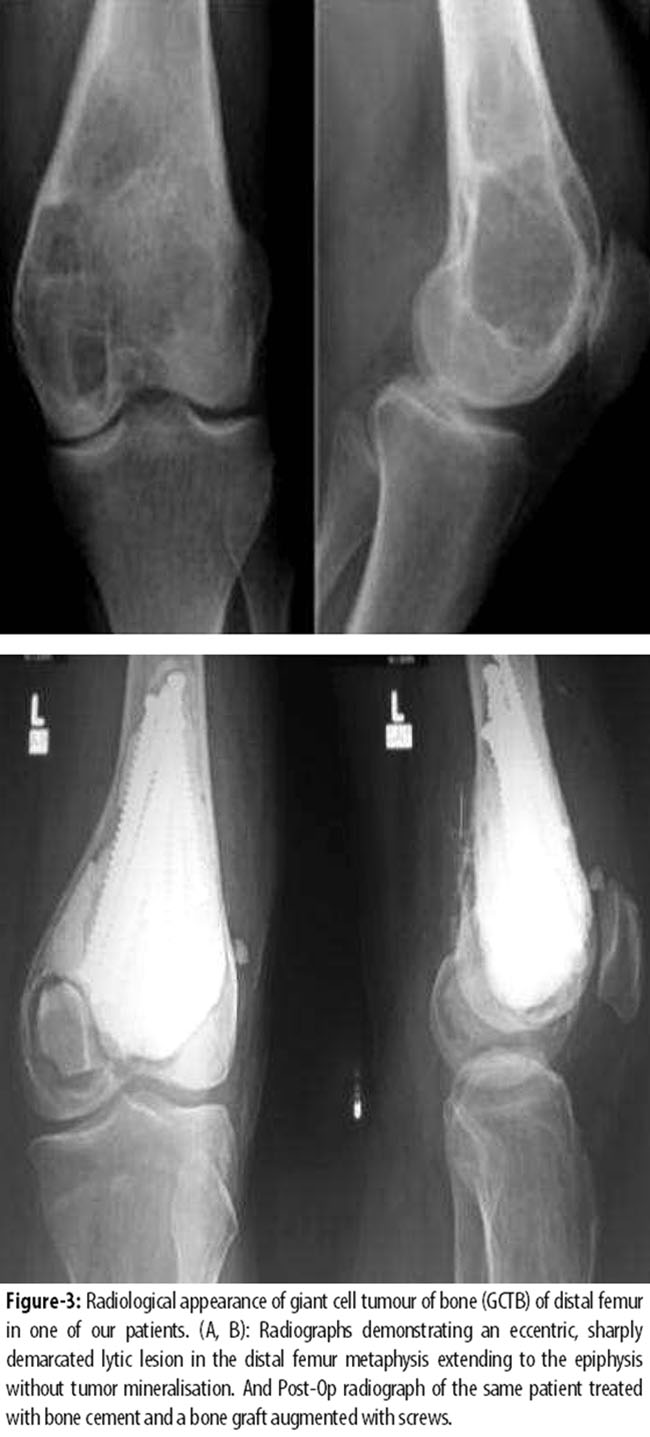

Intralesional procedures were the most common surgical treatment and of the 16(94%) patients treated with intralesional surgery and PMMA void filling, 7(43.7%) received additional local phenol and alcohol treatment; 3(43%) with PMMA and 4(57%) with phenol alone. Six (37.5%) patients were treated solely with PMMA and no additional adjuvants. Wide resections were performed in 1(5.88%) patient (Figure-3, 4),

Reconstructions after wide resections included arthroplasties 1(5.88%), (Figure-4) The mean interval between surgery and recurrence was 16.3±12.4 months (range: 4-36 months) (Figure-5).